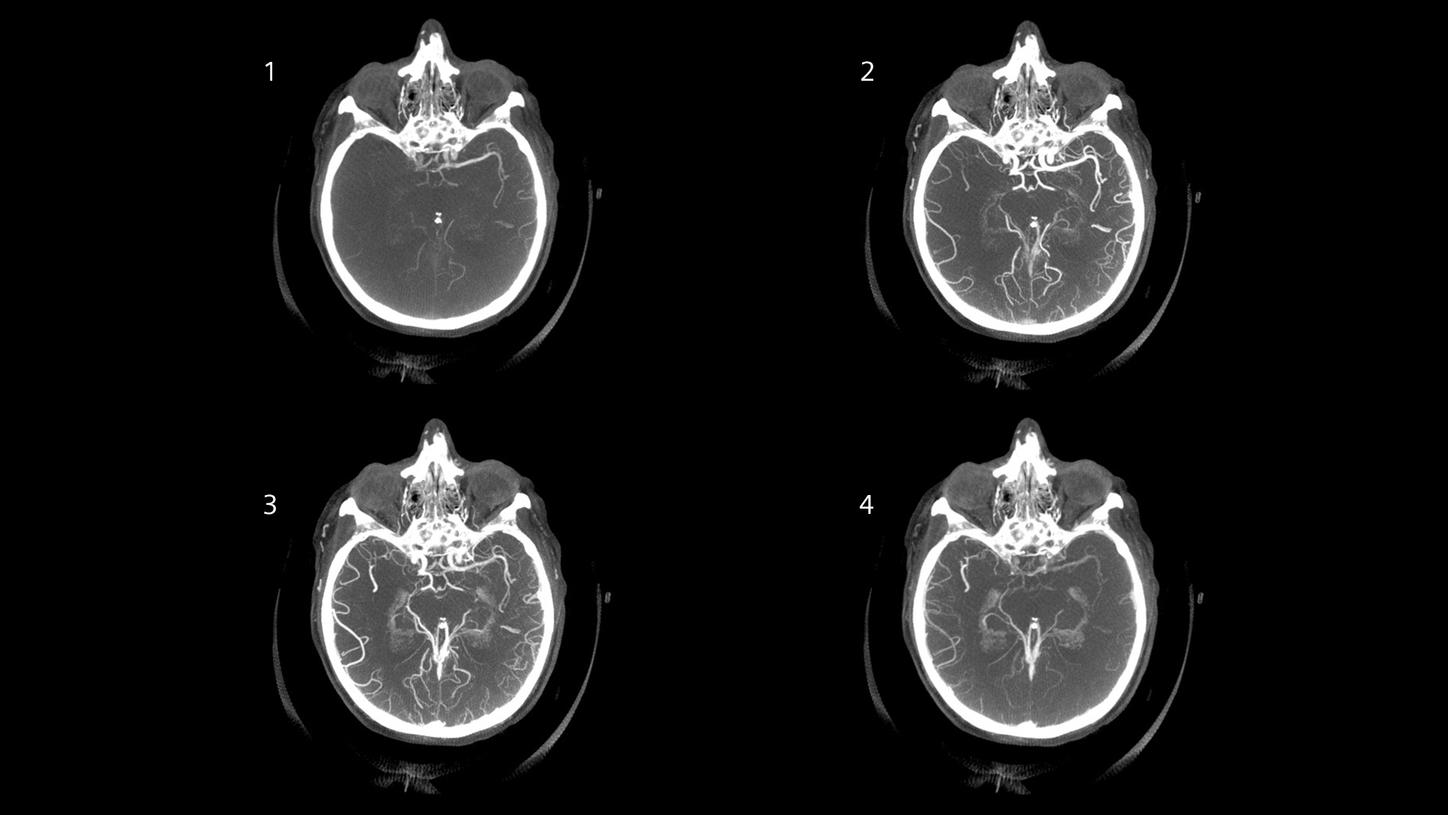

Native head scan

Assist with or support differential diagnosis of acute stroke with excellent gray-white matter differentiation and contrast enhancement

Perfusion scan

Evaluation of infarct core and penumbra by automatically providing perfusion maps for further treatment decisions

Angiography

CT planning of the following treatment with definition of occlusion length and collateral status and automated bone removal

Native head scan

Assist with or support differential diagnosis of acute stroke with excellent gray-white matter differentiation and contrast enhancement

Perfusion scan

Evaluation of infarct core and penumbra by automatically providing perfusion maps for further treatment decisions

Angiography

CT planning of the following treatment with definition of occlusion length and collateral status and automated bone removal